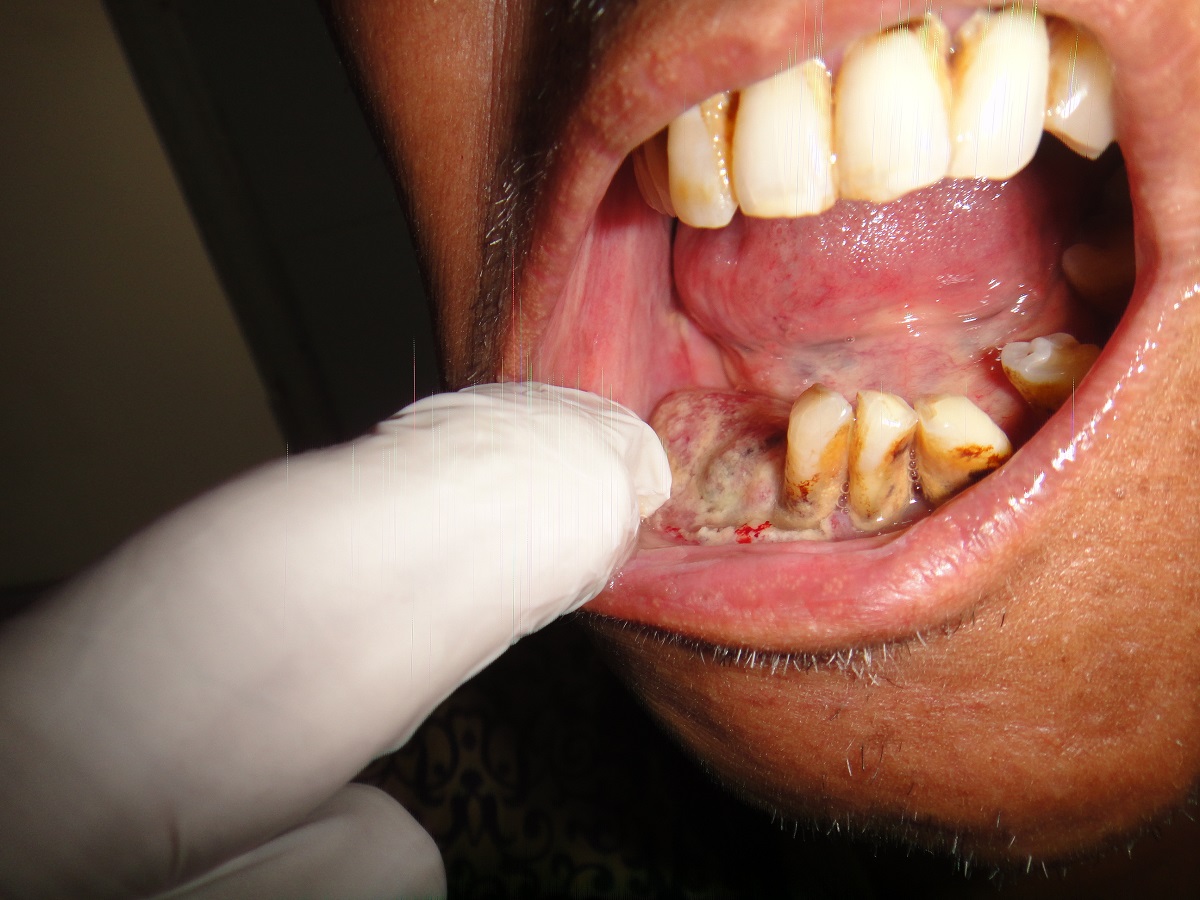

72 YRS LADY HAVING HABBIT OF PUTTING TOBACCO IN THE MOUTH WHILE SLEEPING.SHE DEVELOPES RIGHT BUCCAL MUCOSA CARCINOMA WHICH INVOLVES LOWER GINGIVO BUCCAL SULCUS WITH EROSION OF THE MANDIBLE.RIGHT RADICAL NECK DISSECTION WITH RIGHT HEMIMANDIBULECTOMY WITH RIGHT PM FLAPE DONE.